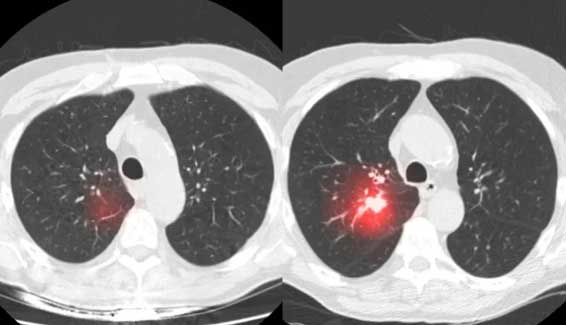

Η Sybil είναι ένα μοντέλο βαθιάς μάθησης το οποίο έχει εκπαιδευτεί σε χιλιάδες αξονικές τομογραφίες. Αξιοποιώντας τις εν λόγω γνώσεις, είναι σε θέση να αξιολογήσει μία αξονική τομογραφία LDCT και να εντοπίσει πρώιμα συμπτώματα της νόσου.

Σύμφωνα με την Regina Barzilay, καθηγήτρια του ΜΙΤ και επικεφαλής της ερευνητικής ομάδας, η Sybil μπορεί να πετύχει εκεί όπου η ανθρώπινη ματιά αποτυγχάνει. Είναι σε θέση να ανιχνεύσει ανεπαίσθητες αλλαγές στις αξονικές απεικονίσεις, προβλέποντας την πιθανότητα ο ασθενής να αναπτύξει καρκίνο του πνεύμονα. Κατά κάποιο τρόπο να προβλέψει δηλαδή το μέλλον.

Η Sybil είναι σε θέση να ανιχνεύσει ανεπαίσθητες αλλαγές στις αξονικές απεικονίσεις.